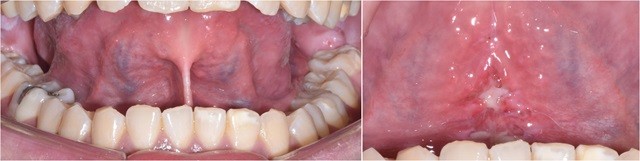

아이가 발음을 또박또박하지 못하거나 혀가 짧아서 일상 대화에서 어려움을 겪는 모습을 간혹 찾아볼 수 있습니다. 만약 아이가 특정한 발음을 하기 어려워한다면 혀 아래에 위치한 얇은 막, 즉 ‘설소대’가 원인일 수 있습니다.

설소대는 혀 움직임의 자유를 좌우하는 구조물로, 혀의 움직임을 조정하고, 구강 기능을 돕는 중요한 역할을 합니다. 설소대가 짧거나 두꺼우면 발음뿐만 아니라 식사, 삼킴에도 영향을 미칠 수 있습니다. 특히 언어 발달 초기 단계를 거치는 영유아의 경우, 발음을 익히는 과정에서 설소대의 이상이 문제가 될 수 있습니다.

만약 설소대 이상으로 인한 불편함을 느낀다면 치과에서 시행하는 ‘설소대 수술’을 통해 개선할 수 있습니다. 설소대 수술은 혀 아래에 위치한 얇은 막(설소대)이 과도하게 짧거나 두꺼워 발음, 삼킴, 식사 등에 영향을 미칠 때 시행되는 간단한 시술입니다. 특히 소아뿐만 아니라 성인에서도 발음이나 구강 기능 개선을 위해 설소대 수술이 시행되기도 합니다.

설소대는 태아가 발달할 때 혀와 바닥 조직이 분리되는 과정에서 발생하는 구조입니다. 이 과정이 불완전하거나 과도하게 이루어지면 설소대가 짧아지거나 두꺼워질 수 있습니다. 설소대가 짧은 경우, 다음과 같은 증상이 나타날 수 있습니다.